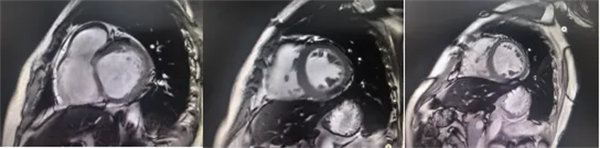

在常規心臟MRI檢查中,醫學影像科發現患者心肌異常表現,考慮鐵過載性心肌病,為明確診斷要進一步加做鐵定量技術,加掃T2 mapping序列。CMR鐵定量技術是目前評估心肌鐵含量的“金標準”,能夠快速、無創、精準量化心肌內鐵沉積程度,檢查結果提示患者局部心肌T2*值顯著低于正常范圍,符合鐵過載性心肌病的診斷標準。

基底部、中間部及心尖部 局部心肌T2*值明顯減低T2* 10-20/s, 部分小于10/s

心肌信號局部減低 呈現“黑色心肌”表現,這是由于鐵沉積導致局部磁場不均勻,引起信號丟失(失相位)。